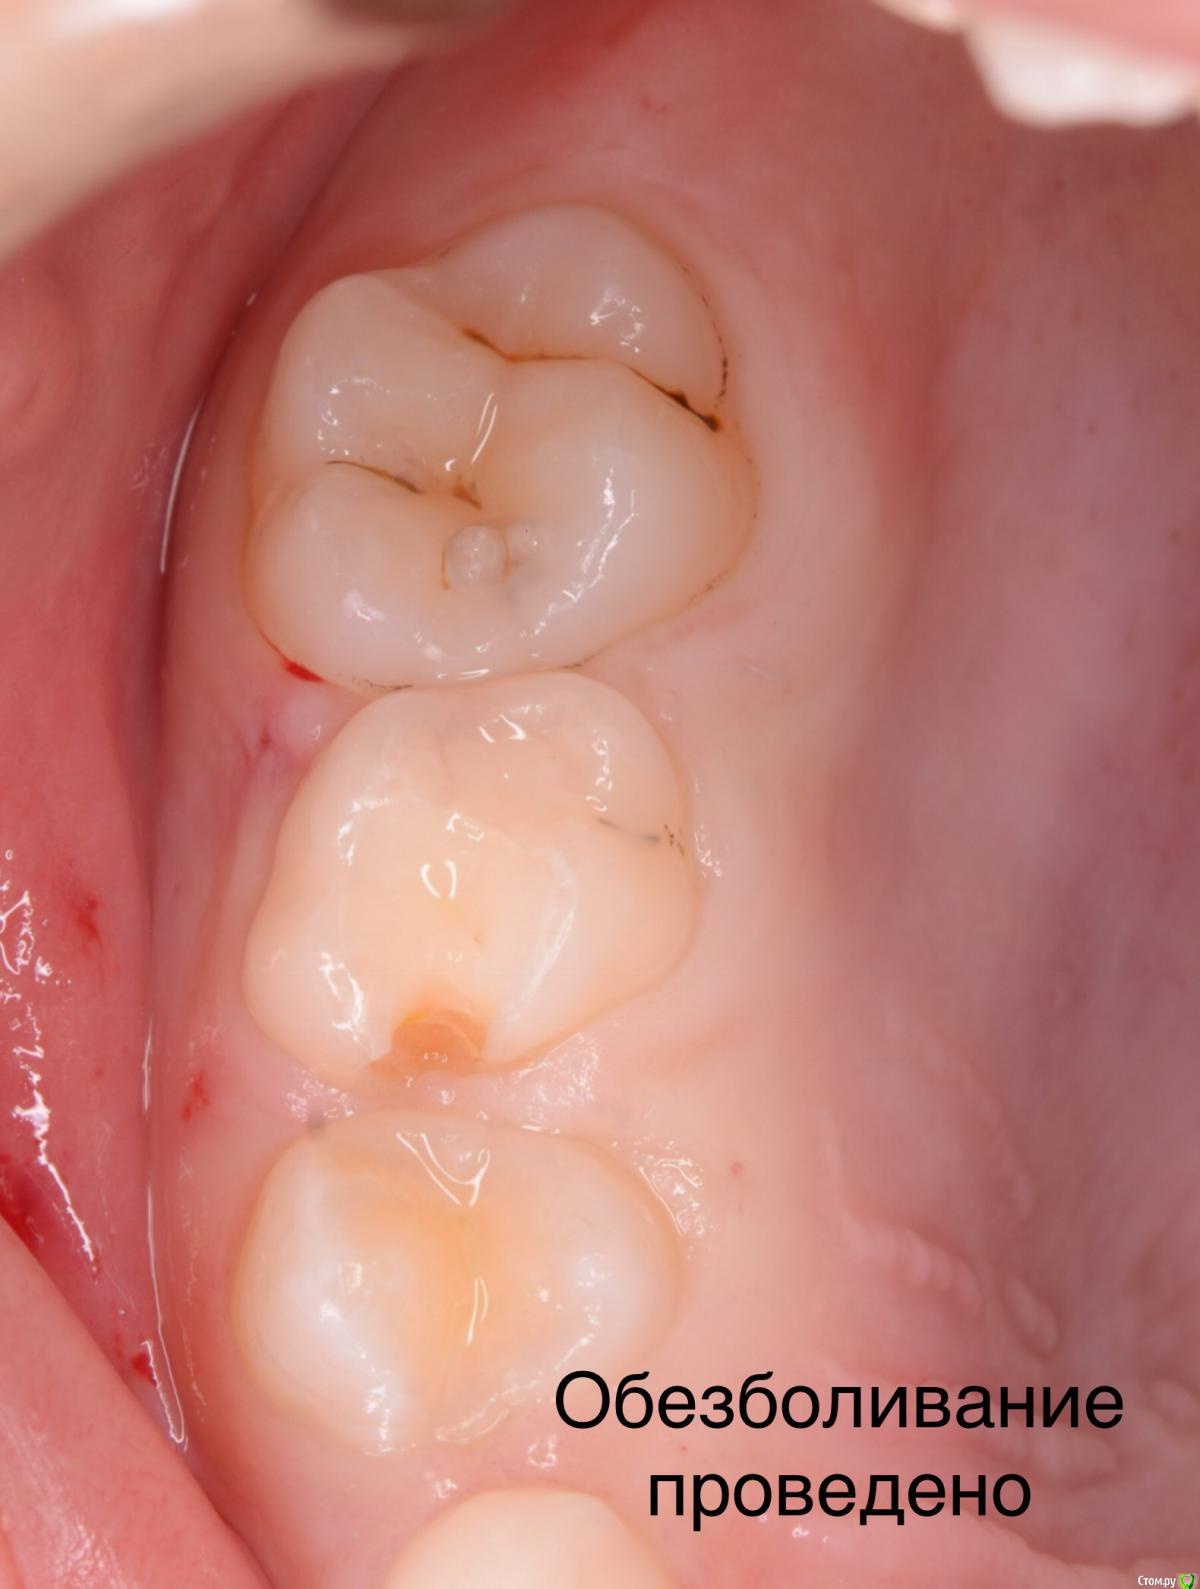

CRAZYDUCK Опубликовано 3 июня, 2018 Автор Поделиться Опубликовано 3 июня, 2018 (изменено) ]Так получается, что и на герметизацию изолируетесь? А как же им в этом случае анестезию там где кламп делаете или он такой что не давит? спасибо ! Анестезия здесь была проведена - лечили же кариес 7.4 зуба. Насчет анестезии - я практически всегда лечу с обезболиванием . Ведь постановка клампа, матрицы , клина неприятные процедуры. Анестезию делаю по книжке Даггала. Сначала инфильтрация , прижимаю создавшееся депо анестетика ватным валиком ненадолго и ввожу по сосочкам медиально и дистально от нужного зуба. На фото анестезия 5.5 зуба. Иголка 30 G 12 мм. После такой анестезии делаю проводниковую если нужно лечить верхние или нижние 6. На такую плавную анестезию уходит карпула, иногда полторы. Изменено 3 июня, 2018 пользователем CRAZYDUCK 1 Ссылка на комментарий

CRAZYDUCK Опубликовано 3 июня, 2018 Автор Поделиться Опубликовано 3 июня, 2018 Итак , фотки . Во время проведения по сосочкам ВАЖНО найти эту точку вкола , чтобы шло так , что на поршень давишь , но умеренно . Бывает вводишь в сосочек, давишь , а анестетик не идёт . А бывает , что наоборот выливается . Ищем другое место вкола , как правило выше ( на верхней челюсти ) и ниже ( на нижней )от первоначального вкола. Это с опытом прийдет . Например , 7.4 кариозная полость дистально и забита пищей , десна воспалена , если вводить в дистальный сосочек , то все будет выливаться из-за воспалённой десны. Нам важно получить побеление ( ишемию кольцевую) . У иглы есть срез . Мы можем после инфильтрации согнуть иглу срезом дистально или медиально . На примере 7.4 - срез иглы направляем дистально и колем в сосочек между 7.3 и 7.4 и десна белеет от клыка к четверке.десна белеет язычно внизу и небно вверху. Это дело практики , и это несложно совсем . 1 Ссылка на комментарий

CRAZYDUCK Опубликовано 3 июня, 2018 Автор Поделиться Опубликовано 3 июня, 2018 (изменено) Фото. Ватные валики рвём напополам и одеваем на иголку , чтобы ее не было видно ( валики проавтоклавированы );перед герметизацией стараюсь одевать коффердам , безболезненно пока одевать не умею , поэтому сначала делаю анестезию . Я перед герметизацией чищу глицином ( каво профифлекс , и ещё рондофлексом могу пройтись 27 мкм оксид алюминия , а без платка - ощущения неприятные Изменено 3 июня, 2018 пользователем CRAZYDUCK 3 Ссылка на комментарий